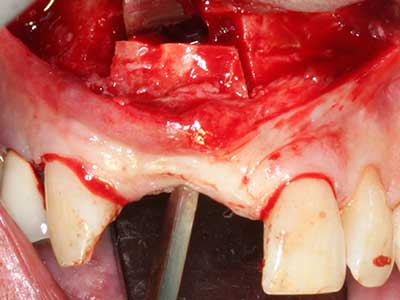

La piezochirurgia presenta altri vantaggi per quanto riguarda la raccolta di blocchi ossei. Oltre all'elevata precisione dell'osteotomia appena descritta, l'utilizzo di puntine per sega molto sottili permette di minimizzare in maniera significativa la perdita di materiale. È molto probabile che si verifichi una maggiore perdita di materiale durante la raccolta utilizzando puntine di strumenti più spessi, in particolare delle frese Lindemann (Lakshmiganthan, Gokulanathan et al. 2012). La separazione basale, necessaria in particolare per i trapianti di blocchi nella zona retromolare, viene semplificata grazie a seghe specificatamente progettate di forma rettangolare; di conseguenza la piezochirurgia è considerata una procedura precisa, semplice e sicura per la raccolta di blocchi di osso nella zona retromolare (Happe 2007) (figg. 1-12).

Il tessuto osseo non è semplicemente una struttura minerale, ma contiene anche una percentuale significativa di fibre di collagene. Ciò significa che non possiede solo una buona forza di compressione, ma anche un certo livello di flessibilità che è possibile sfruttare durante l'esecuzione degli accrescimenti di osso. Nella procedura di espansione classica con incisione ossea, la cresta alveolare atrofizzata viene incisa longitudinalmente ed espansa con cautela dopo aver raggiunto una profondità di osteotomia adeguata (figg. 13-16), idealmente senza una sostanziale rimozione del periostio (Brugnami, Caiazzo et al. 2014, Stricker, Fleiner et al. 2014). I sistemi a piastra e vite con distanza di espansione incrementale si sono dimostrati efficaci nella separazione delle due lamelle ossee restando al di sotto della soglia di frattura. In generale, sono richieste larghezze dell'osso residuo di almeno 3-4 mm (Chiapasco, Zaniboni et al. 2006) per garantire un'adeguata flessibilità e una copertura sufficiente dell'osso per gli impianti futuri. Se necessario, un'osteotomia di rilascio verticale su uno o più lati può migliorare la flessibilità. Una combinazione con ulteriori tecniche di accrescimento, in particolare dal lato buccale, è stata descritta come un'alternativa alla tecnica classica.

La procedura di incisione è particolarmente atraumatica e non comporta una perdita significativa di dimensione durante l'utilizzo delle seghe piezoelettriche, così come non si notano differenze rilevanti tra impianti in mandibole incise e impianti in una cresta alveolare senza deficit osseo (Chiapasco, Zaniboni et al. 2006, Danza, Guidi et al. 2009). Una sufficiente irrigazione continua è essenziale, tuttavia, in particolare con incisione profonda e localmente ristretta, per prevenire la sollecitazione termica nelle regioni apicali dell'osteotomia.